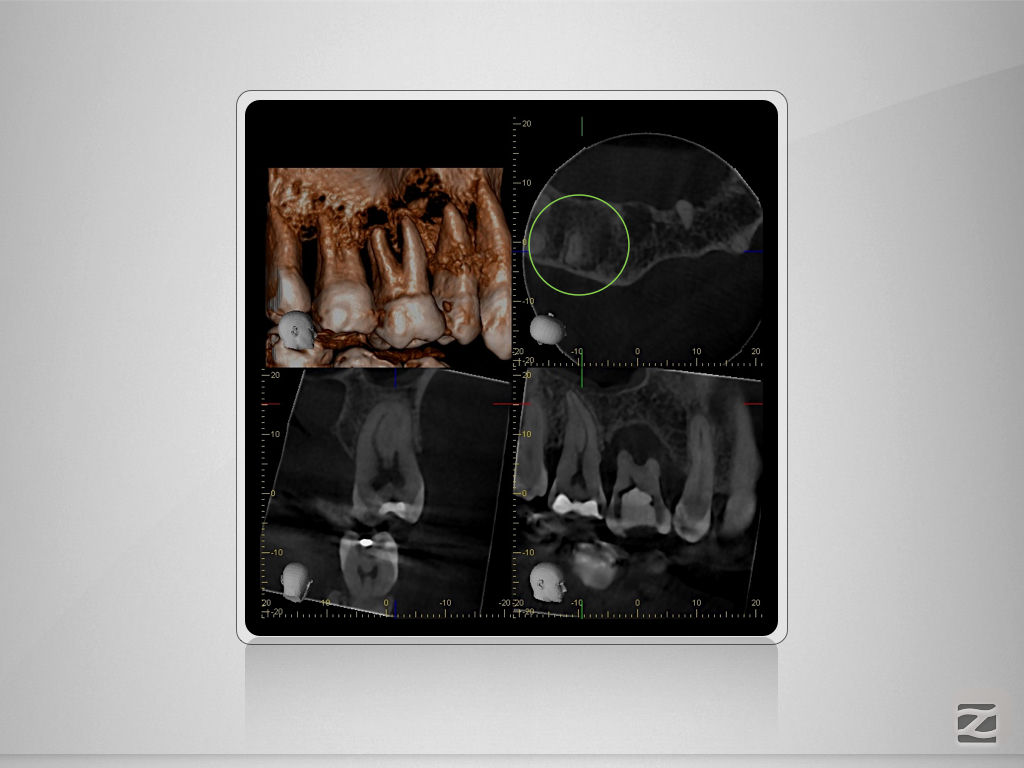

17D.010

Gewusst, wo’s lang geht.